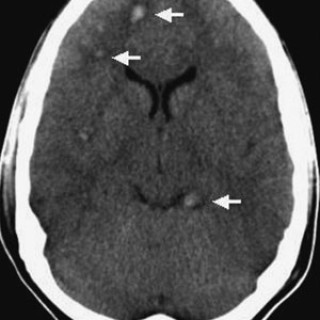

Hodeskader inndeles klinisk etter alvorlighetsgrad. I Skandinavia brukes ofte Head Injury Severity Scale (1), og skaden graderes da i kategoriene minimal, lett, moderat og alvorlig. Klassifikasjonen er i hovedsak basert på skår etter Glasgow Coma Scale (GCS), og opplysninger om bevissthetstap og/eller amnesi (tab 1). En pasient med GCS-skår 3 er dypt bevisstløs og reagerer ikke på smerte, mens en pasient som har GCS-skår 15, er helt våken, klar og orientert og kan utføre bevegelser på oppfordring. Et hodetraume kan føre til fokal skade, diffus skade eller til en kombinasjon av disse to. Fokale...